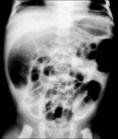

腸道氣囊腫症1.腹部平片 採取臥位及直立位平片,攝片前宜清潔灌腸。當氣囊小、數量又少時,多無特徵性表現,若氣囊大而多,尤其位於漿膜下,則可見:①充氣腸曲的邊緣可見聚簇或波浪狀的連續囊狀透光區,大小不等,自粟粒至葡萄大小,直徑通常1~2cm;②氣囊破裂形成氣腹時,立位片可見膈下游離氣體;③間位腸曲征(Chilaiditi)是氣腹時氣體積於橫膈和肝或胃底之間,使膈升高,肝或胃底下降,造成相當大的間隙,充氣的腸曲易上升而進入間隙內,形成間位腸曲,氣囊腫的腸曲更易形成間位,使腸壁的確良囊狀透光區顯示更清晰,此征出現對該病診斷幫助甚大。